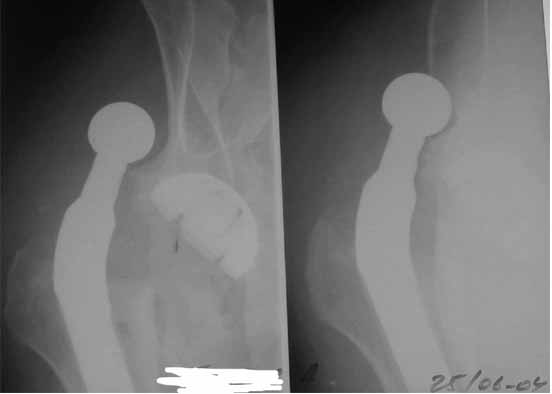

AAY> Желательно иметь рентгенограммы как после операции так и после

AAY> вправления вывиха.

Я думал, это не очень важно. Вышлю и во время вывиха. Я просто не успел отснять их, а товарищ мой немного торопил - волнуется.

Во вложении - рентгенограммы после вывиха и после вправления.

Идея очень простая, в случае, если удасться прожить без вывиха 2.5-3 месяца, вероятность его возникновения в будущем значительно уменьшится. Оптимальный вариант - повторная иммобилизация на срок 6 недель с нагрузкой на ногу (как бы я ни не любил гипс, но этот путь проверенный и может дать результат). Если это невозможно, то исключительно осторожная реабилитация под строгим контролем без резких движений (спать в положении на спине с отведением и подушкой под коленкой и т.д.). Ходьба сама по себе не опасна, опасен переход от положения "лежа" в положение "полусидя" и "стоя" и наоборот.